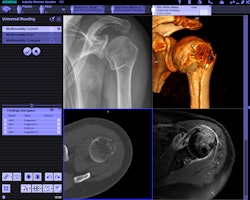

| Syngo via is designed to support primary 3D image interpretation. All images courtesy of Siemens Healthcare. |

While client-server 3D platforms have been available for the past several years, Siemens believes that syngo via is unique in two aspects: its emphasis on support for multimodality images rather than just large multislice CT datasets, and its incorporation of workflow algorithms designed to make the use of 3D more efficient and less time-consuming.

For example, cases like cardiac CT angiography are preprocessed to perform steps like bone removal and artery segmentation prior to delivery to the radiologist. Siemens engineers also developed an improved user interface designed to optimize the image interpretation process, giving radiologists more screen real estate to improve concentration, Montag said. Little mouse interaction is required, which enables radiologists to keep their eyes on images. The software can function as a reporting tool as well.

Syngo via is vendor-neutral and works with any company's images, Montag said, but users of Siemens equipment will be able to take advantage of specialized acquisition and viewing applications, and via's workflow-optimization tools work best when the information is shared with a Siemens modality scanner.